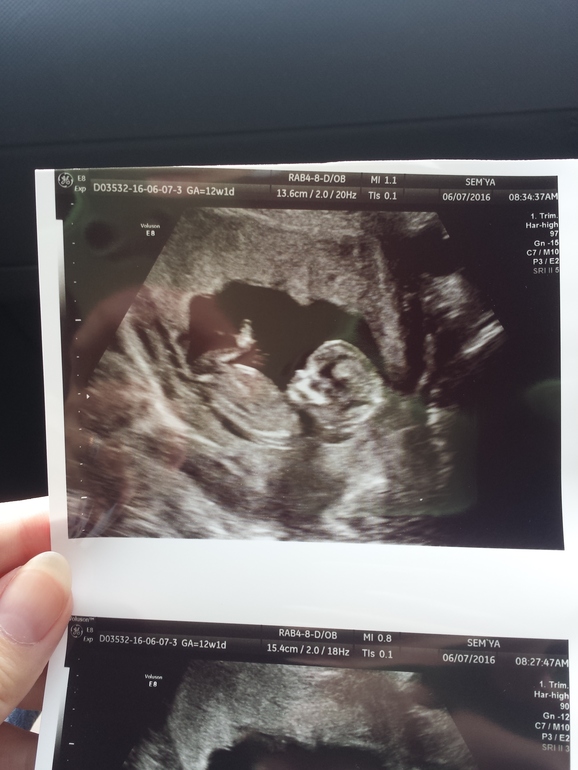

Всем привет!!!!как же долго я здесь не писала)отдыхала у своих родителей в деревне,а там с инетом проблемы.как же здорово с мамой и папой,даже уезжать не хотелось,но скоро прилетает муж(наконец-то мы с крошкой дождались).мы растем,как только приехала в город сразу побежала на узи)))не скрининг,а просто узи)скрининг у нас 5 августа.все хорошо,все в норме,вес 280 грамм(вот думаю не много ли для 18.5 недель?)чсс 165,степень зрелости плаценты 0,толщина 2см,прикрепление по передней стенке,центральное.головное предлежание.а вот пол показывать мы не хотим,пуповину промеж ног засунул)))наверное папочку ждет)))первые толчки начались в конце 17 недели,сейчас становятся все чаще и отчетливее.я счастлива)жду мужа и 2 скрининга!и первое фото животика)все говорят животик большой и что мальчик будет)на первом скрининге предположили мальчика.еще фото с первого скрининга приложу,посмотрите,как думаете,кто будет???))))